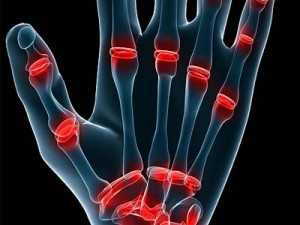

- Хруст, локализованный в суставах рук. Многие считают, что щелкать суставами пальцев не вредно. Однако не всегда подобные

звуки являются безобидными. Если длительно игнорировать проявляющиеся симптомы, то хрящевая ткань начинает постепенно изнашиваться, следствием чего становится развитие артроза. Чтобы этого избежать необходимо, делать регулярный массаж рук и легкие физические упражнения для кисти и пальцев. - Неприятные звуки в спине. Подобное щелканье в большинстве случаев становится следствием сильного давления на сустав, при этом оно во много раз превышает привычное сопротивление, которое испытывают мышцы и связки. Обычно это считается нормой. Но когда щелчок становится частым явлением, то это говорит о том, что мышцы сильно перенапряжены и перегружены, поэтому не в силах самостоятельно выдерживать данную нагрузку. Неприятные звуки в спине могут возникнуть в результате инфекционных заболеваний, неправильного питания, постоянного нахождения в одном положении тела и чрезмерных физических нагрузках. Очень важно суметь уберечь позвоночник от подобных неприятностей, ведь в будущем это грозит развитием тяжелых болезней.